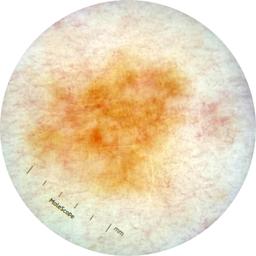

ISIC_7193897

1979 x 1979

Clinical

Field Value

acquisition_day 251

age_approx 65

anatom_site_1 Lower extremity

anatom_site_general lower extremity

concomitant_biopsy False

diagnosis_1 Benign

diagnosis_confirm_type single image expert consensus

family_hx_mm False

image_manipulation instrument only

image_type dermoscopic

lesion_id IL_3780211

patient_id IP_3751325

personal_hx_mm True

sex female